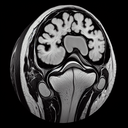

МРТ грудного відділу хребта

Магнітно-резонансна томографія (МРТ) грудного відділу хребта – це неінвазивний метод діагностики, який використовується для отримання детальних зображень цього сегмента хребта. ### Коли необхідне МРТ грудного відділу: 1. **Больові відчуття**: Стійкий чи сильний біль у спині, який не минає після стандартного лікування...